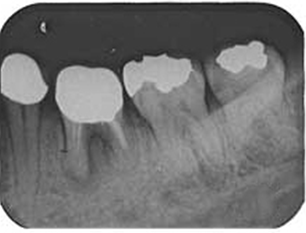

左下奥歯の虫歯が大きく被せ物が取れてきた右上の親知らずを 移植希望の30歳男性

BEFORE

金属の被せ物が取れて、歯の根の方まで虫歯が進行してしまっているため抜歯をしました。

初診時のレントゲン写真です。 向かって右から2番目。歯が割れているため、根のまわりが黒くなっています。 ここにカラー写真の向かって右から1番目の親知らずを移植します。

AFTER

移植し歯を固定ました。

移植から一週間後、根の治療をし土台を立て(写真左)、クラウンを被せました。(写真右)。